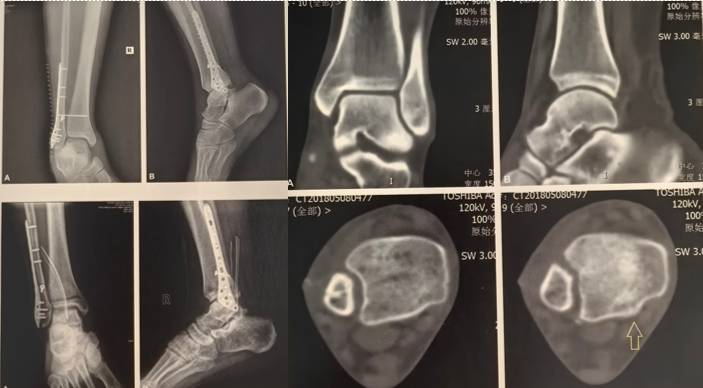

二、诊断要点:

X线:

AP位:胫腓重叠(tibiofibular overlap)

侧位:距骨后脱位、腓骨后移

CT(金标准):

确认腓骨移位

显示后踝骨折类型

发现隐匿性骨折(Tillaux、Wagstaffe)

首先通过X线片、CT明确骨折类型及骨折细节,此例腓骨骨折属于WeberB型,通过CT发现内侧间隙增大,考虑三角韧带损伤的可能较大,同时后踝骨折块较小。

作者选择后外侧入路,先复位腓骨,后踝未予处理,未予三角韧带修补,复位腓骨后检查下胫腓间隙不稳定行下胫腓螺钉固定。术后CT可见下胫腓间隙复位可。作者术中通过复位外踝、下胫腓间隙后透视见内踝间隙匹配可。